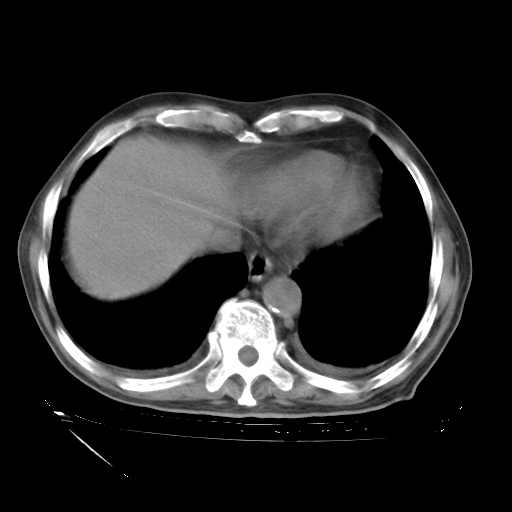

补充下:5月9日胸部CT:似乎已见双下肺胸腔积液了,鉴于目前有下肢水肿,肝功示:白蛋白低,应注意多浆膜腔积液(漏出液可能大?),需注意!

甲强龙80mg/日+抗结核治疗(异烟肼+利福霉素+乙胺丁醇)10天。复查肺部CT。

治疗10天肺部CT